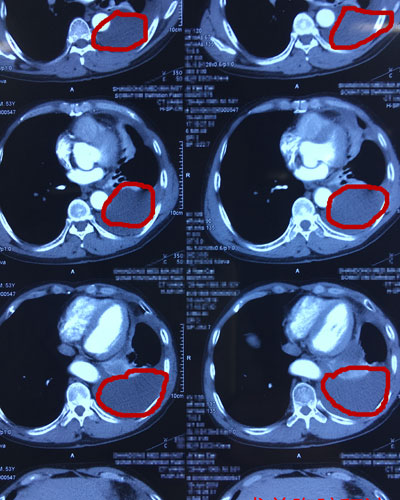

桑梓店院区第一时间将CT传给了胸外科隋刚主任。隋刚主任看过CT并了解了病情后,立即回复桑梓店院区,可以通过手术治疗患者胸腔反复积液。当天,患者就从桑梓店院区转诊到了省立三院胸外科。

针对患者的病情,胸外科隋刚主任为患者制定了“胸腔镜下胸膜固定术”的治疗方案。在山东省立第三医院手术室、供应室的密切配合下,胸外科隋刚主任带领许世宁副主任医师成功为患者实施了“胸腔镜下滑石粉胸膜固定术”。

术中,通过一个2厘米的小 切口,将滑石粉喷涂在脏、壁层胸膜的表面,使胸膜腔广泛黏连防止胸膜渗出。术后当晚,患者就可以平卧休息了,极大改善了生活质量。患者的女儿激动的说:“看着爸爸日夜那么痛苦,我们全家都绝望了,幸好遇上了隋刚主任!”